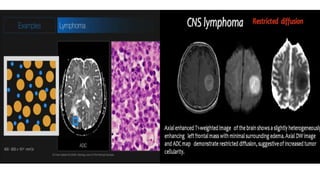

CLINICAL APPLICATIONS OF DWI

NEUROIMAGING applications :

1. Stroke

2. Epidermoid vs arachnoid cyst

3. Abscess vs simple cystic lesion

4. DWI in brain tumors

DWI in BODY IMAGING: